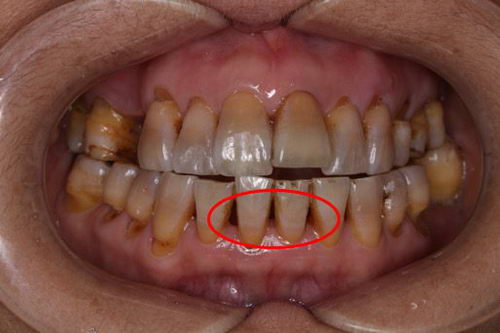

这张图就是牙周炎症导致牙龈退缩,从而出现的黑三角症状。在这种情况下,食物残留很容易发生,所以更加需要彻底地清洁牙齿邻接面,否则出现牙齿松动脱落的几率将会大大增加。